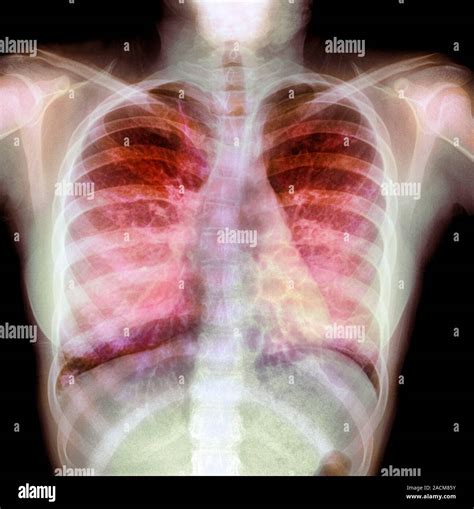

Dealing with mucus in chest can be an incredibly frustrating and uncomfortable experience. Whether it is a lingering side effect of a common cold, a sign of seasonal allergies, or a symptom of a more persistent respiratory condition, that heavy, congested feeling often makes every breath feel like a chore. While mucus is a natural part of your body's immune defense system, designed to trap irritants and pathogens, an excessive buildup can obstruct your airways and lead to coughing, wheezing, and general fatigue. Understanding why this buildup occurs and how to manage it effectively is the first step toward breathing easier and restoring your daily comfort.

Mucus, or phlegm, is produced by the mucous membranes lining your respiratory tract. Under normal circumstances, it is thin and watery, helping to keep your airways moist and trapping dust or allergens. However, when you become ill or are exposed to environmental triggers, your body ramps up production to fight off invaders. When this mucus becomes too thick or is produced in large quantities, it becomes difficult for your cilia—the tiny, hair-like structures in your lungs—to move it out, resulting in that dreaded mucus in chest sensation.